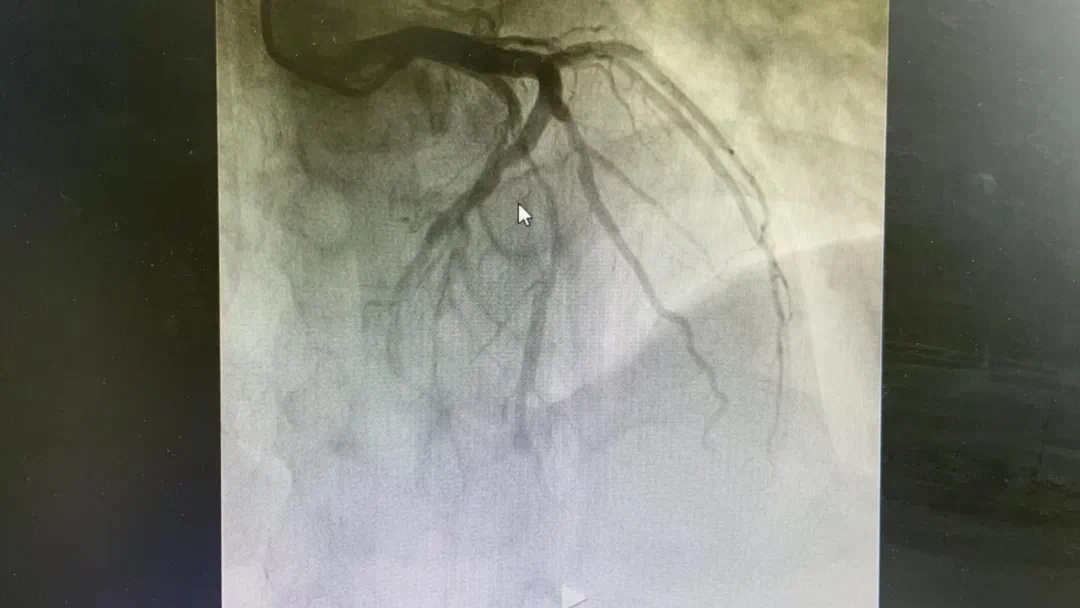

晚22点40分,胸痛中心的手术还在进行中,急诊科又打来电话告知患者张某胸痛、头痛3小时,高敏肌钙蛋白异常。

术前、术后图片如下

副主任何涛、医师熊俊锋、护士张梅梅顾不上休息,立刻投入到第三次抢救中。胸痛中心团队心内科与急诊科无缝衔接,23点26分在导管室开通堵塞血管,又成功救治一名急性心肌梗死患者。患者张某送至导管室施行急诊冠脉介入治疗,经过快速的术前准备,以mini Crush术式于回旋支远段植入波科冠脉支架一枚,再于钝缘支中段至回旋支中段植入Firebird2冠脉支架一枚。患者症状大幅缓解。零点42分手术结束,复查患者血压、心率正常后将患者送回病房。